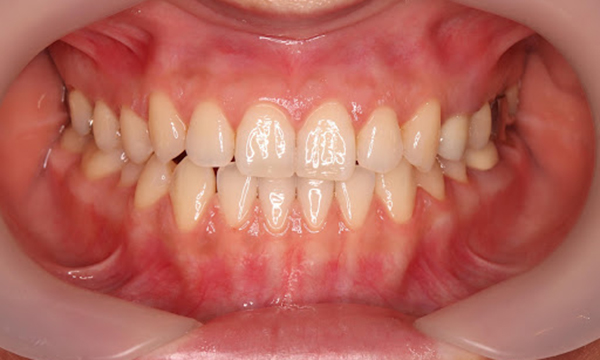

症例

症例1

Before

after

基本情報

年齢・性別 52歳・男性

主訴 主訴:久しぶりの歯医者なので歯石をとってほしい

治療部位:全顎

治療内容 1.歯磨き指導、歯肉縁上の歯石除去

2.歯磨きの確認、指導(磨けるようになるまで)

3.歯磨きの確認、指導、歯肉縁下の歯石除去(SRP)

4.PMTC

5.再評価、歯磨きの確認、指導

治療期間 1日

治療費 合計17,560円

・内訳

1、歯周基本検査・歯磨き指導、縁上スケーリング:1,800円

2、歯周精密検査・SRP(スケーリング・ルートプレーニング)、歯磨き指導:2,130円

3、SRP、歯磨き指導:3回(1,530円×3回)

4、PMTC、全顎再スケーリング、歯磨き指導:5,500円(自費診療)+1,260円

5、再評価(歯周精密検査)、歯磨き指導:2,280円

※PMTC以外、保険診療3割負担

(2023年5月現在現在)

リスク・副作用 ・毎日の歯磨きが不十分だと歯石を除去しても再度歯石がついてしまう

・最初は歯磨きのときに出血してくることがあるが、細菌が減って歯茎が引き締まってくると徐々に出血は落ち着いてくるため痛みがなければ辛抱強く磨いてもらう

・歯周病は時間をかけて静かに進行する病気なので、歯周病を治すにはそれなりに期間がかかる、すぐには治らない

・歯ぐきが引き締まると歯茎が下がり歯間に隙間ができる可能性がある

治療方針 一時的な治癒ではなく、将来的にこの治療が活かされるよう、患者さん自身である程度自己管理ができるようになることを目標とした

特記事項 ふつうのブラシと電動歯ブラシ使用(ブラウン丸型使)

歯間ブラシを1日1回は最低でも使って頂いた

担当者所見 あまり器用な方ではなかったため、決まったところがいつも磨けず奥歯に歯間ブラシがなかなか入れられませんでしたが、歯間ブラシのサイズを変えてみたり、内側から入れてみたりと試行錯誤してなんとかある程度磨けるようになりました。

その結果、出血が100%から7%へ激減することができました。

ただSRPをしただけではここまでの結果は出なかったと思います。

それほど日々のセルフケアが重要だということを再認識しました。

歯周ポケットが残っている部位、出血がある部位に関しては引き続き歯磨きを念入りに行なってもらう。